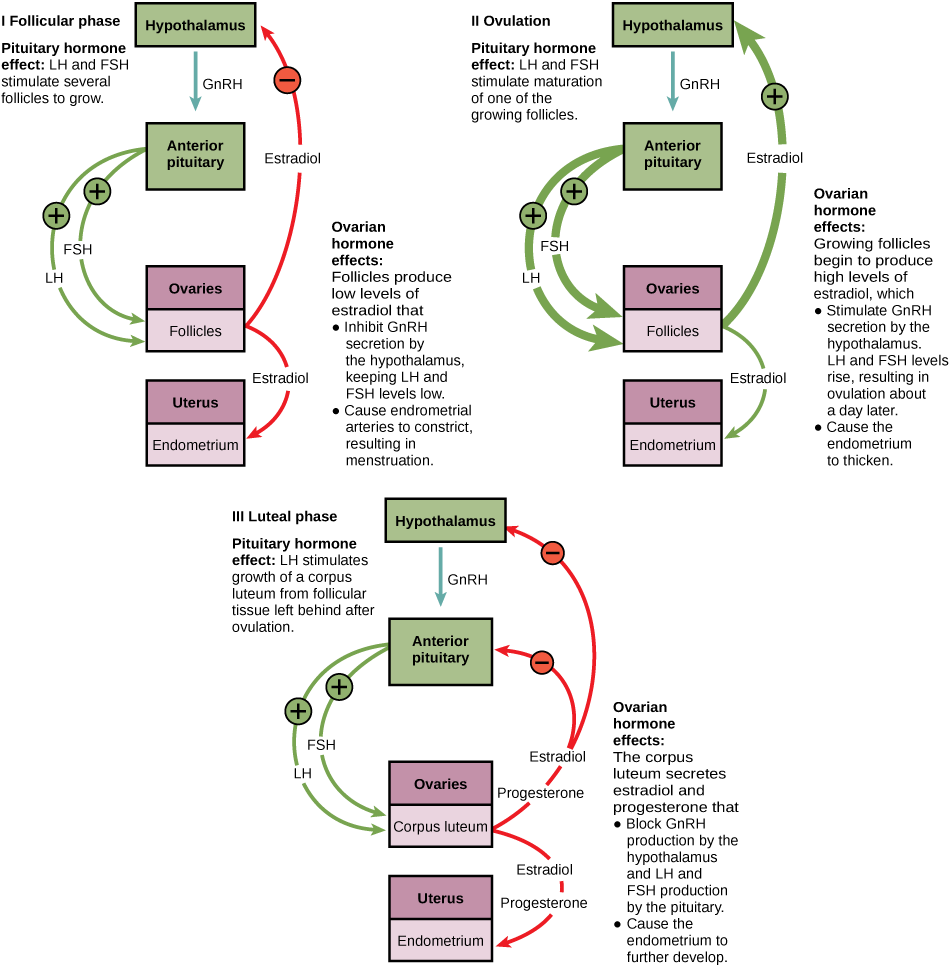

The control of reproduction in females is more complex. As with the male, the anterior pituitary hormones cause the release of the hormones FSH and LH. In addition, estrogens and progesterone are released from the developing follicles. Estrogen is the reproductive hormone in females that assists in endometrial regrowth, ovulation, and calcium absorption; it is also responsible for the secondary sexual characteristics of females. These include breast development, flaring of the hips, and a shorter period necessary for bone maturation. Progesterone assists in endometrial regrowth and inhibition of FSH and LH release.

In females, FSH stimulates development of egg cells, called ova, which develop in structures called follicles. Follicle cells produce the hormone inhibin, which inhibits FSH production. LH also plays a role in the development of ova, induction of ovulation, and stimulation of estradiol and progesterone production by the ovaries. Estradiol and progesterone are steroid hormones that prepare the body for pregnancy. Estradiol produces secondary sex characteristics in females, while both estradiol and progesterone regulate the menstrual cycle.

The first half of the ovarian cycle is the follicular phase shown in Figure. Slowly rising levels of FSH and LH cause the growth of follicles on the surface of the ovary. This process prepares the egg for ovulation. As the follicles grow, they begin releasing estrogens and a low level of progesterone. Progesterone maintains the endometrium to help ensure pregnancy. The trip through the fallopian tube takes about seven days. At this stage of development, called the morula, there are 30-60 cells. If pregnancy implantation does not occur, the lining is sloughed off. After about five days, estrogen levels rise and the menstrual cycle enters the proliferative phase. The endometrium begins to regrow, replacing the blood vessels and glands that deteriorated during the end of the last cycle.

Which of the following statements about hormone regulation of the female reproductive cycle is false?

- LH and FSH are produced in the pituitary, and estradiol and progesterone are produced in the ovaries.

- Estradiol and progesterone secreted from the corpus luteum cause the endometrium to thicken.

- Both progesterone and estradiol are produced by the follicles.

- Secretion of GnRH by the hypothalamus is inhibited by low levels of estradiol but stimulated by high levels of estradiol.

Just prior to the middle of the cycle (approximately day 14), the high level of estrogen causes FSH and especially LH to rise rapidly, then fall. The spike in LH causes ovulation: the most mature follicle, like that shown in Figure, ruptures and releases its egg. The follicles that did not rupture degenerate and their eggs are lost. The level of estrogen decreases when the extra follicles degenerate.

Following ovulation, the ovarian cycle enters its luteal phase, illustrated in Figure and the menstrual cycle enters its secretory phase, both of which run from about day 15 to 28. The luteal and secretory phases refer to changes in the ruptured follicle. The cells in the follicle undergo physical changes and produce a structure called a corpus luteum. The corpus luteum produces estrogen and progesterone. The progesterone facilitates the regrowth of the uterine lining and inhibits the release of further FSH and LH. The uterus is being prepared to accept a fertilized egg, should it occur during this cycle. The inhibition of FSH and LH prevents any further eggs and follicles from developing, while the progesterone is elevated. The level of estrogen produced by the corpus luteum increases to a steady level for the next few days.

If no fertilized egg is implanted into the uterus, the corpus luteum degenerates and the levels of estrogen and progesterone decrease. The endometrium begins to degenerate as the progesterone levels drop, initiating the next menstrual cycle. The decrease in progesterone also allows the hypothalamus to send GnRH to the anterior pituitary, releasing FSH and LH and starting the cycles again. Figure visually compares the ovarian and uterine cycles as well as the commensurate hormone levels.

Figure Which of the following statements about hormone regulation of the female reproductive cycle is false?

- LH and FSH are produced in the pituitary, and estradiol and progesterone are produced in the ovaries.

- Estradiol and progesterone secreted from the corpus luteum cause the endometrium to thicken.

- Both progesterone and estradiol are produced by the follicles.

- Secretion of GnRH by the hypothalamus is inhibited by low levels of estradiol but stimulated by high levels of estradiol.

Figure C